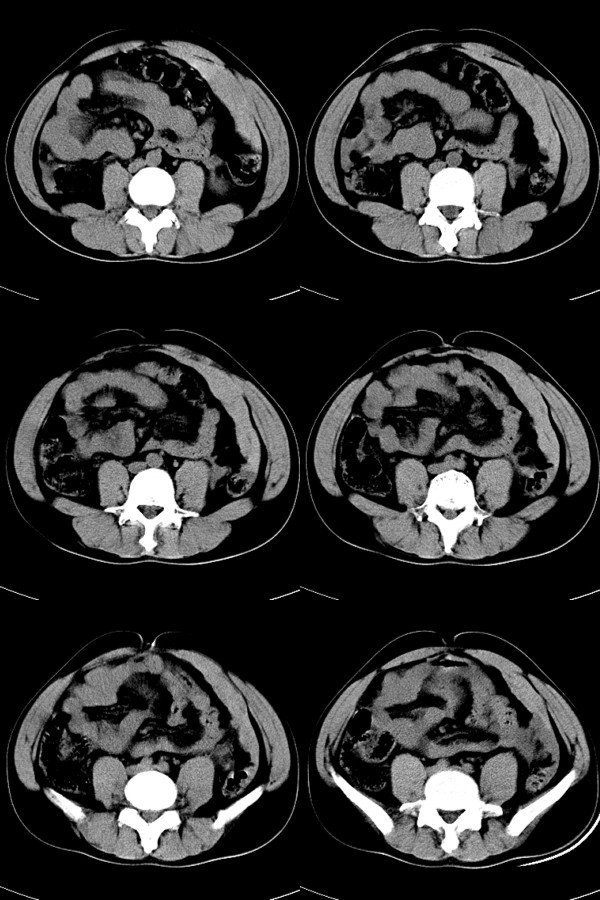

标题: CT17991:M32y,腹部外伤。

32岁男性,外伤后腹部、腰部疼痛。腹部压痛明显,呈“板状腹”。既往体健。

请指教红色箭头所示为什么影像?

红箭所示为腹膜腔积血

腹膜腔积血,考虑:腹腔脏器损伤!

腹腔血肿(前侧腹壁下)

前左侧腹壁下腹腔血肿。

箭头为腹膜外血肿;;建议使用w300---500;l负50--70,可清晰显示腹腔游离气液影,有利空腔器官破裂诊断

腹膜腔积血